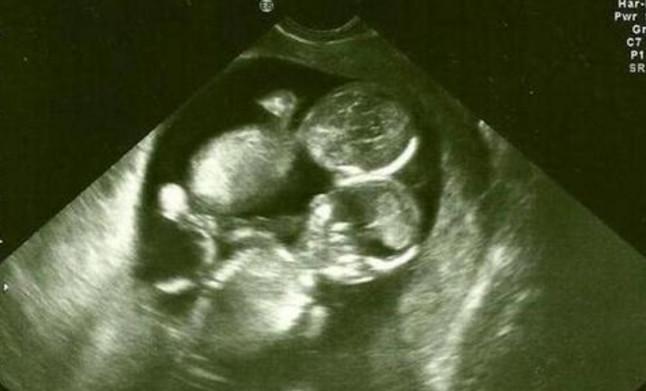

一位女子就很幸运的怀上了三胞胎的孩子,但是这位女子并没有定期的去做产检,这位女子在怀孕五个月的时候去做产检的时候,女子才知道自己怀上了三胞胎孩子,不过医生却说有两个孩子是连体的宝宝。

本来怀上三个宝宝是一个多么高兴的事情,但是知道两个宝宝是连体婴儿之后,女子和丈夫都是不知道要怎么接受的,后来夫妻两人经过商量了之后就决定要做减胎的手术,夫妻两人都是希望可以把这个健康的宝宝生下来。